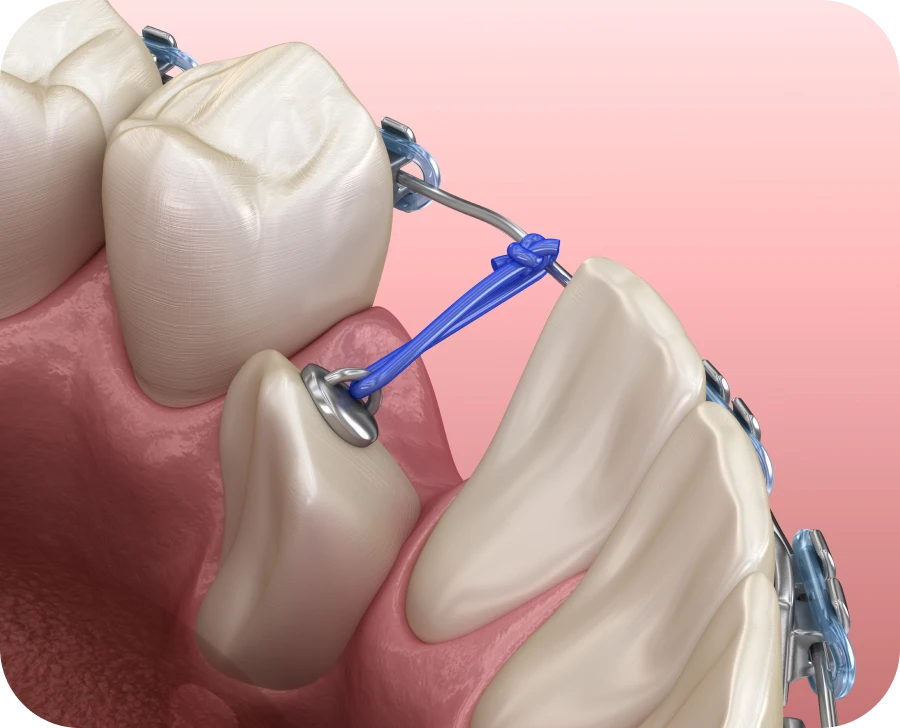

Par la suite, une traction orthodontique est souvent mise en place. Une attache est alors fixée sur la dent, qui est doucement guidée à l’aide d’un fil. Il convient d’ajuster progressivement la force de traction afin de ne pas fragiliser la racine. Des rendez-vous réguliers permettent de suivre l’évolution et de réajuster le traitement si besoin.

Certaines dents sont plus souvent concernées par une inclusion. C’est notamment le cas des canines maxillaires. Leur éruption doit être surveillée dès l’âge de 9 ans. Lorsqu’elles sont orientées vers le palais, une désinclusion chirurgicale est souvent nécessaire. Un traitement interceptif permet alors de dégager leur chemin d’éruption. Une fois la dent exposée, une attache collée permet de guider sa progression vers la bonne position.